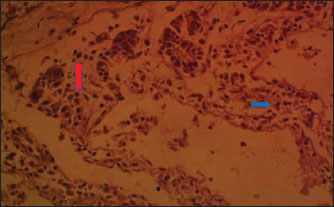

Fig. 3. (PBLM): Section of the intestine showing moderated necrosis of Crept of Lieberkühn (blue arrow) and mucosal (arrow head) epithelial cells, with infiltration of inflammatory cells (red arrow) (x400; H & E).

In the NLM shown in Figure 1, the mucosal lining was complete, with the Lieberkühn villi and crypts properly arranged. The epithelial layer, largely composed of absorptive enterocytes and goblet cells, was well preserved and did not show cellular erosion or necrosis (An et al., 2022). The lamina propria appeared to be free of inflammatory infiltrations, and the make-up was not atrophied or distorted, indicating a healthy mucosal barrier and optimum operational capacity (France and Turner, 2017). The TDLM (Fig. 2) had effects that showed cellular disintegration of the Lieberkühn crypts, signifying epithelial rejuvenation (Liu et al., 2019). At the same time, mucosal epithelial inner layer necrosis, shown by disturbed cellular structure and cytoplasmic degradation, suggests a distorted mucosal barrier that may amplify absorptivity, poor nutrient assimilation, and increased susceptibility to enteric pathogens (Chistiakov et al., 2014; De Medina et al., 2014). These observed changes can be due to the secondary metabolites like saponins, alkaloids, phenolics, and tannins present in Tithonia diversifolia, which are known to cause cytotoxic, anti-proliferative, and membrane-disrupting activities in the GIT tract when taken unprocessed (Abdelsalam and Fathi, 2023). These observations demonstrate the need for detoxification, quantification, and probably fermentation when incorporating TDLM into the diet of local rabbits (Abd-Elghany et al., 2021). Although TDLM provides a good source of nutritious and phytogenic benefits, its raw inclusion must be controlled to avoid compromising gut integrity and performance (Sugiharto et al, no date). In the observed PBLM in Figure 3, the necrosis in the crypt of Lieberkühn shows disturbance of the proliferative region crucial for epithelial regeneration and intestinal homeostasis (Chistiakov et al., 2014). Impairment of the crypts affects enterocyte production, which may cause weakened absorptive and digestive effectiveness in the small intestine (Buckley and Turner, 2018). Concurrently, mucosal epithelial cell degeneration and necrosis show intestinal barrier failure, increasing the danger of luminal antigen translocation and mucosal susceptibility (An et al., 2022). The permeation of inflammatory cells, mainly lymphocytes and macrophages, demonstrates a limited immune response that may be a reaction to epithelial injury caused by phytochemicals in Parkia biglobosa leaves (Franz et al., 2019). These bioactive constituents possess antioxidant and antimicrobial properties and may cause cytotoxic effects at high levels of inclusion in unprocessed form. Tannins and saponins can tamper with membrane integrity, modify gut microflora, and trigger mucosal irritation (De Medina et al., 2014). These effects are consistent with the inflammatory and degenerative changes observed in the duodenal mucosa (Chistiakov et al., 2014; De Medina et al., 2014). The observed necrosis in the crypt that controls epithelial cell production and mucosal renewal in rabbits fed SNLM indicates weakened cellular turnover (Buckley and Turner, 2018). Moreover, the loss of mucosal epithelial cells’ integrity shows that the absorptive and protective barrier is compromised, which is crucial for nutrient uptake and host protection (Liu et al., 2022). The infiltration of inflammatory cells, principally comprising lymphocytes and plasma cells, into the lamina propria, as shown in Figure 4, demonstrates an ongoing immune response that may have been prompted by mucosal or antigenic disturbance from biologically active compounds in Synedrella nodiflora. If the concentration is not regulated, this can lead to a cytotoxic or pro-inflammatory effect on the mucosa of the GIT (Jha et al., 2019). Specifically, saponins are known to disrupt membranes and increase gut penetrability, possibly leading to reactionary inflammation and epithelial damage (Ohimain et al., 2020). Necrosis of the Lieberkühn crypt observed in the LMM (Fig. 5) and damage to the mucosal epithelial cells affect the intestinal epithelium, compromising absorptive and secretory activities crucial for gut health (Buckley and Turner, 2018). This pattern is consistent with that observed in other leaf meals; however, the infiltration of inflammatory cells appeared mild, suggesting a moderate but continuous controlled immune response, possibly to clear away cellular fragments and restore mucosal integrity (Chistiakov et al., 2014; De Medina et al., 2014). This trend aligns with subacute intestinal damage, where soreness is present but not distressing, enabling mucosal recovery if the injurious stimuli are removed (France and Turner, 2017; An et al., 2022).